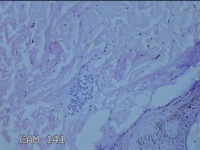

右侧臀部结节

性别

男

年龄

27岁

临床诊断

皮脂腺囊肿

一般病史

发现右侧臀部结节3年余。

标本名称

大体所见

灰白暗红色组织1.2x0.7x0.3cm一块,表面带梭形皮肤1x0.7cm,皮下见结节1.2x0.7x0.3cm一个,切开结节呈实性,切面灰白暗红色,质软。